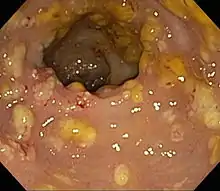

| Pathological specimen showing pseudomembranous colitis | |

Prior to the advent of tests to detect C. difficile toxins, the diagnosis most often was made by colonoscopy or sigmoidoscopy. The appearance of "pseudomembranes" on the mucosa of the colon or rectum is highly suggestive, but not diagnostic of the condition.[45] The pseudomembranes are composed of an exudate made of inflammatory debris, white blood cells. Although colonoscopy and sigmoidoscopy are still employed, now stool testing for the presence of C. difficile toxins is frequently the first-line diagnostic approach. Usually, only two toxins are tested for—toxin A and toxin B—but the organism produces several others. This test is not 100% accurate, with a considerable false-negative rate even with repeat testing.[46]

Pseudomembranous colitis first was described as a complication of C. difficile infection in 1978,[110] when a toxin was isolated from people with pseudomembranous colitis and Koch's postulates were met.